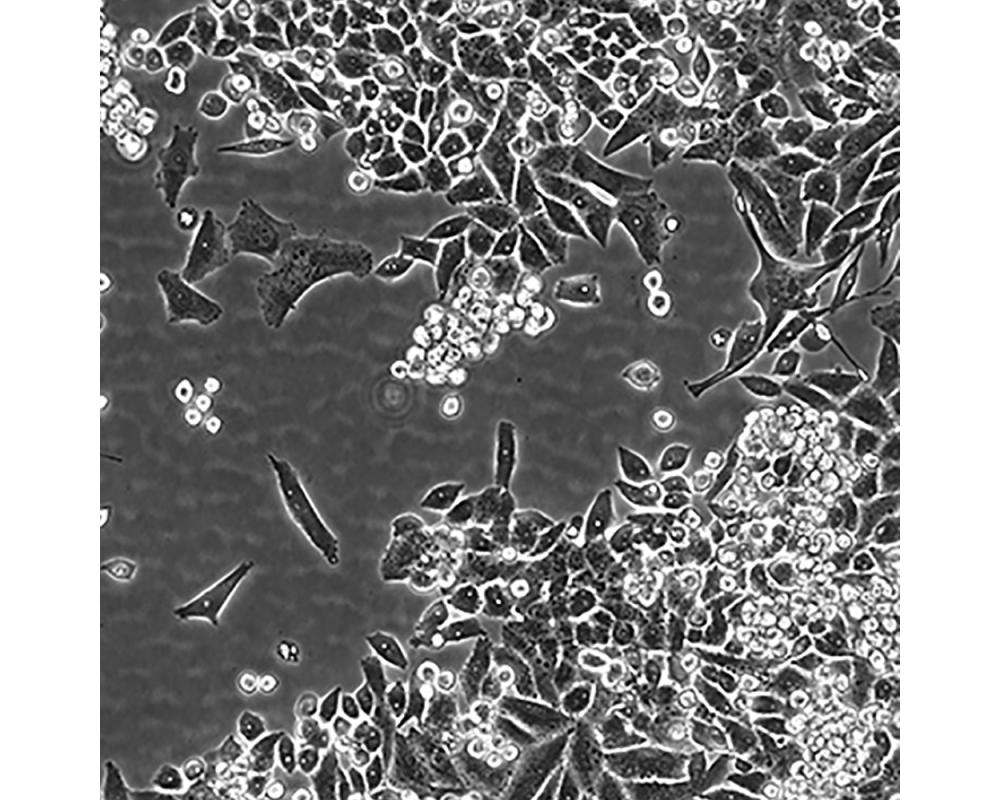

MiaPaCa-2

中文名稱 人胰腺癌細(xì)胞

組織來(lái)源 胰腺導(dǎo)管癌;男性

生長(zhǎng)特性 貼壁